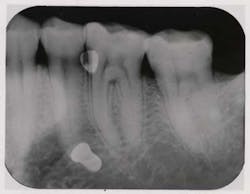

The new AIR-FLOW PERIO technology developed by EMS takes air polishing where access was previously denied: the periodontal pocket. Treatment with the EMS AIR-FLOW PERIO Method has been evaluated in peer review literature and found to be safe, effective and efficient. The method removes biofilm in five seconds per site. Also, patients perceive this conservative treatment to be more comfortable than SRP.How is subgingival air polishing possible? First, consider the powder. Developed specifically for subgingival application with the AIR-FLOW PERIO devices, the EMS AIR-FLOW powder PERIO is glycine-based, which has approximately 1/5 the abrasiveness of sodium bicarbonate, and is capable of removing biofilm in just 5 seconds. This PERIO powder, along with the specially designed, disposable PERIO-FLOW nozzle tips and reduced air pressure, allows for safe application of the air-powder-water mixture into the pocket. The resulting biokinetic energy of the air-powder-water mixture in the pocket removes biofilm up to 5 mm. The patented PERIO-FLOW nozzle has three horizontal outlets for the air and powder and one vertical outlet for water to optimize the mixture in the pocket and prevent soft tissue emphysema.The original AIR-FLOW PERIO Method is now available in two EMS devices. The AIR-FLOW Master combines sub- and supragingival AIR-FLOW technologies in one tabletop device. The AIR-FLOW handy PERIO, a portable subgingival air-polisher that conveniently attaches to a high speed handpiece cord is portable. For more information, visit www.ems-dent.com or call (800) 367-0367.To read more about EMS, go to EMS.To comment on this product, go to community.pennwelldentalgroup.com/.